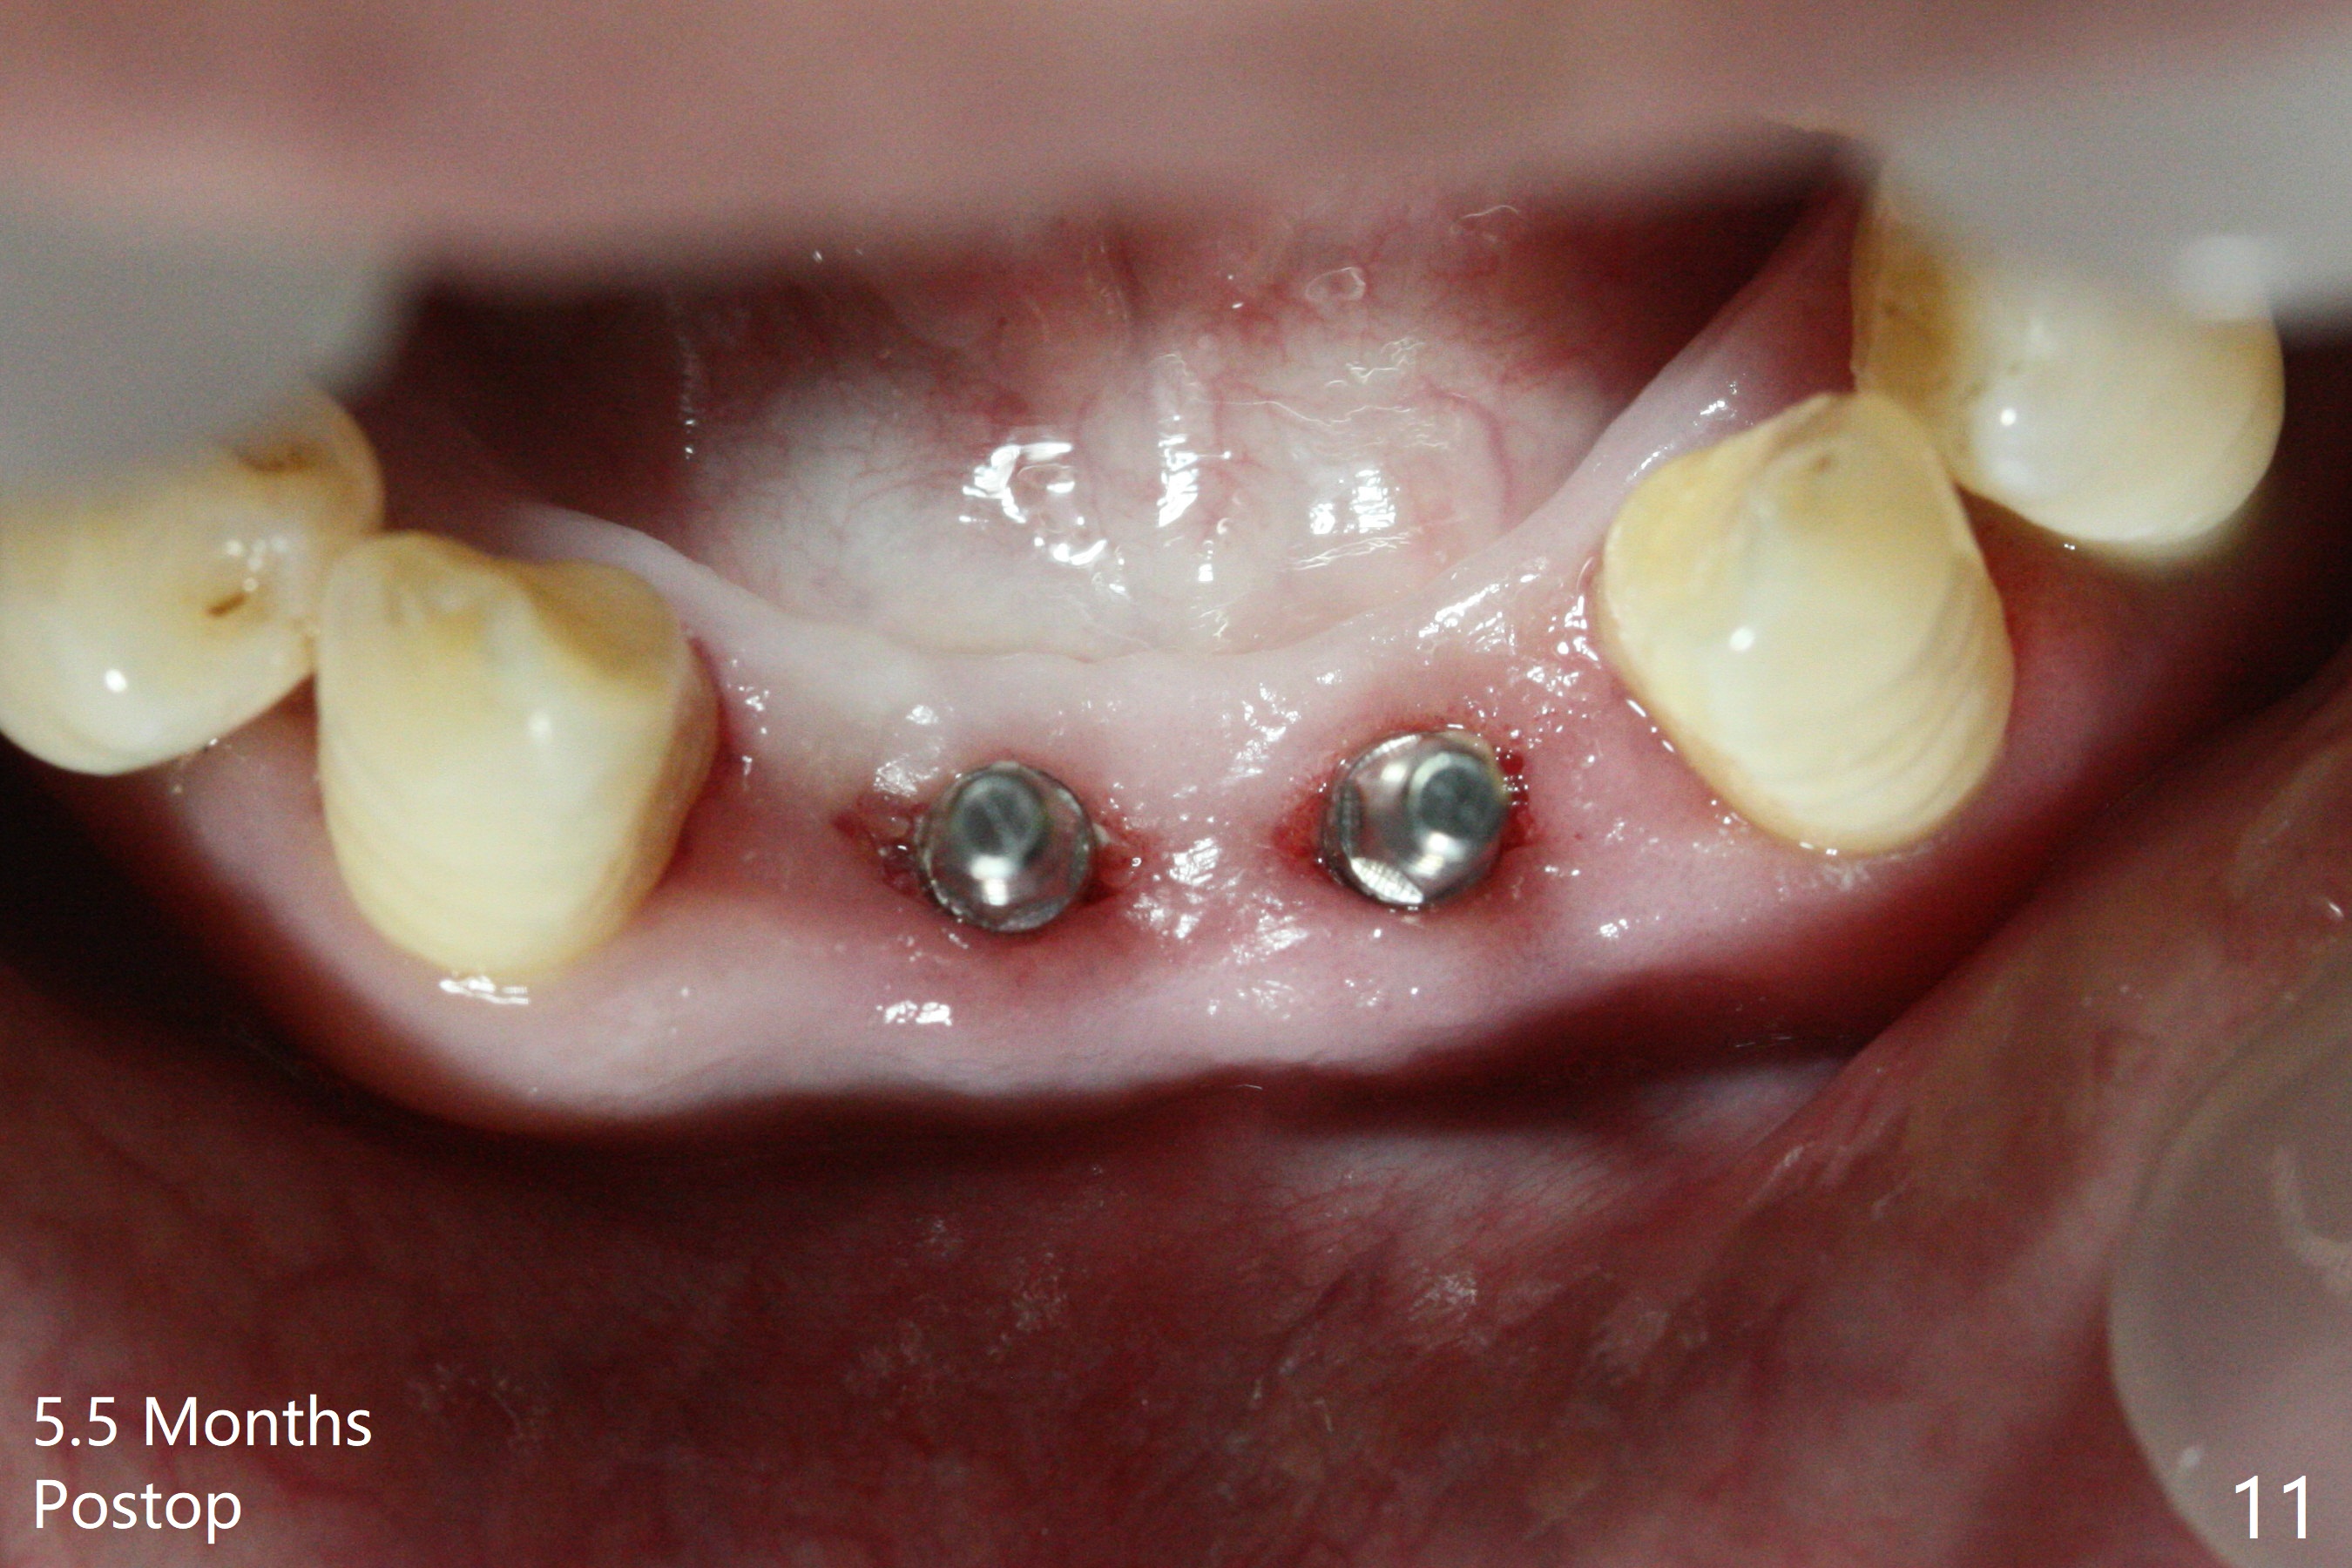

After extraction of 4 of the lower incisors, there are basically 2 sockets (#23/24 and 25/26), separated by the apparently midline bone (Fig.1 red line). In spite of using Lindamann bur to move the 25/26 osteotomy mesially, a 3x14(2) mm dummy implant remains close to the tooth #27 (Fig.2). The terminal branch of the Incisive Canal (<) is located between the lateral and central incisors. A de novo osteotomy (Fig.3 (1.5 mm drill)) is made mesial to the original one (O). While the 3x14(2) mm dummy implant is incompletely placed at #25/26, a 3x14(4) mm 1-piece one is placed at #23/24 (Fig.4). Finally the same implant is placed at #25/26 with placement of mineralized cortical/cancellous bone (Fig.5 *). When the large sockets are sutured, the supraerupted teeth #7-9 touch the lower gingiva (Fig.6). The incisal edge is reduced for clearance (Fig.7). Periodontal dressing is less likely to be dislodged with the incisal edge reduction (Fig.8,9). A provisional FPD is fabricated 1 week postop. Hard (Fig.10) and soft (Fig.11,12) tissues heal 5.5 months postop. The patient returns for crown cementation 3 months post impression (9 months postop, Fig.13,14).